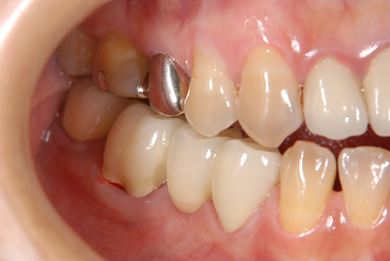

主訴 右下の奥歯をセラミックで治療したい。

治療前

• 治療前